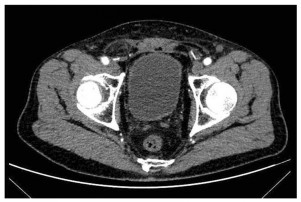

入院后进行相关的实验室检查,血常规提示血红蛋白为82 g/L。肝功能、肾功能、电解质、凝血相关指标、CEA、CA19-9、细胞角蛋白正常。下腹部CT扫描显示膀胱后壁弥漫性增厚,周围组织边界不清,见图 1。CT扫描还显示左侧输尿管积液,左侧肾盂扩张和左侧肾周积液,未发现明显的淋巴结肿大或远处转移。膀胱镜活检病理提示:(膀胱)高级别浸润性浆细胞样尿路上皮癌,HE染色见图 2。免疫组织化学:CK(+),P40(+),P63(+),CK高(+),CK7(+),CK8/18(+),CK20(+),CD138(+),CD38(-),CD56(-),CK5/6(-),EMA(-),Desmin(-),Vimentin(-),Syn(-),CgA(-),LCA(-),MUM-1(-),Ki-67(+,约80%)。

| 图 1 患者治疗前CT扫描显示膀胱弥漫性增厚 Figure 1 Pretreatment CT scan showed diffuse bladder thickening |